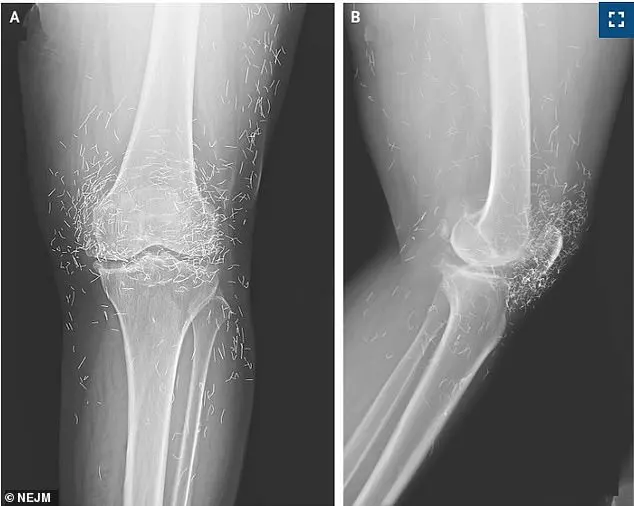

A 65-year-old woman in South Korea, seeking relief from osteoarthritis pain, found herself in a medical quandary when an X-ray of her knee revealed an unexpected and alarming discovery: hundreds of gold threads embedded deep within her joints.

The X-ray images showed not only signs of osteoarthritis but also clusters of metallic specks concentrated around her kneecaps, extending into her shin bone and upper thigh.

These threads, though marketed as inert and beneficial, had become a source of ongoing discomfort and potential complications.

The specks on the X-ray obscured critical anatomical structures, complicating the assessment of her condition and delaying proper treatment.